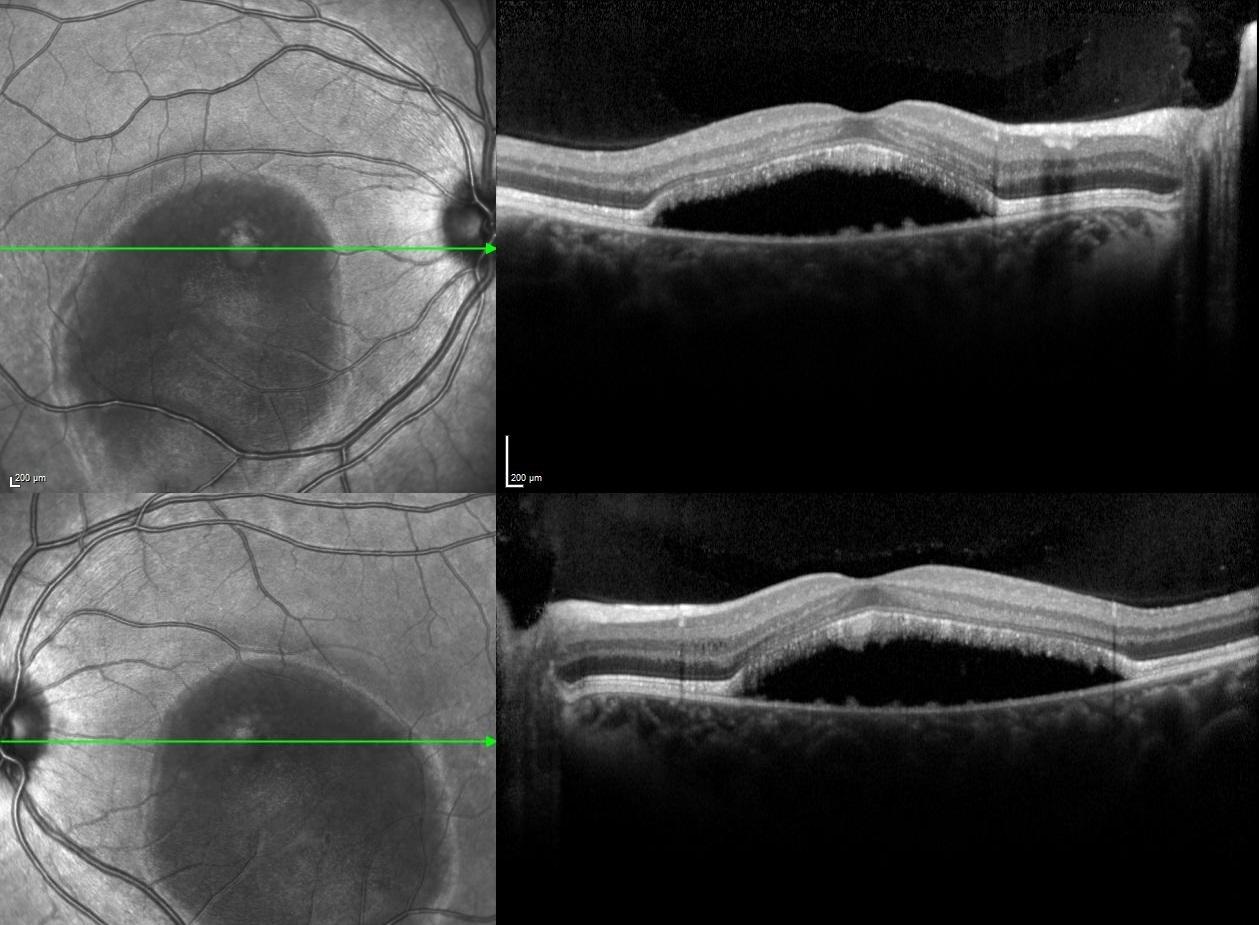

Spectral-domain optical coherence tomography illustrated hyporeflective serous macular detachment with vitelliform deposits along the floor in both eyes.

The natural history of Best disease can progress through five possible stages, including pseudohypopyon (Stage III) and vitelliruptive (Stage IV) stages, which might be notable for serous macular detachment and large subretinal hyporeflective spaces observed under spectral-domain optical coherence tomography. The presence of serous macular detachment may lead the practitioner to assume that an exudative process is present, thus leading to unnecessary and inappropriate treatment.